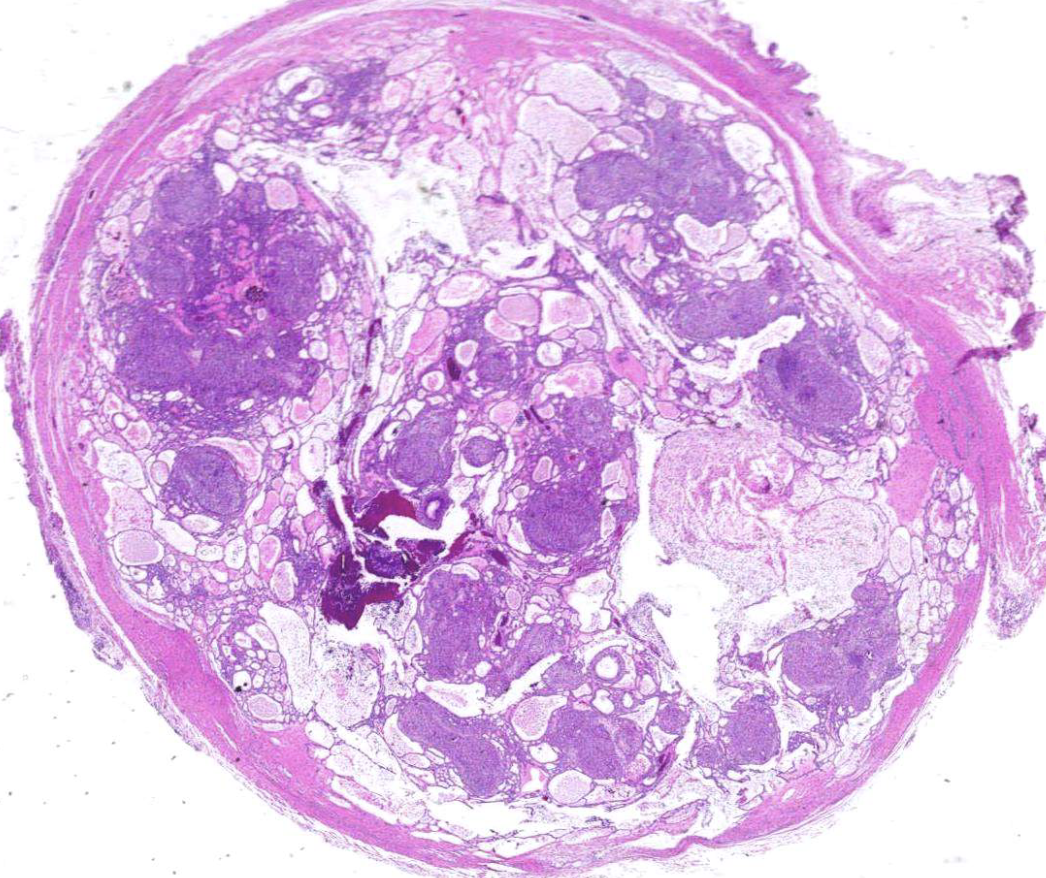

follicular pattern hisopath features of ameloblastomas

nests of epithelium

island centers resembling stellate reticulum

peripheral columnar cells with nuclei polarized opposite basement membrane (sub-nuclear vacuolization)

mature fibrous background

histopath features of adenomatoid odontogenic tumors

well-defined lesion surrounded by thick fibroud capsule

tubular or duct-like structures

histopath features of calcifying epithelial odontogenic (Pindborg) tumors

islands, strands, or sheets of epithelial cells in fibrous stroma

Liesegang rings